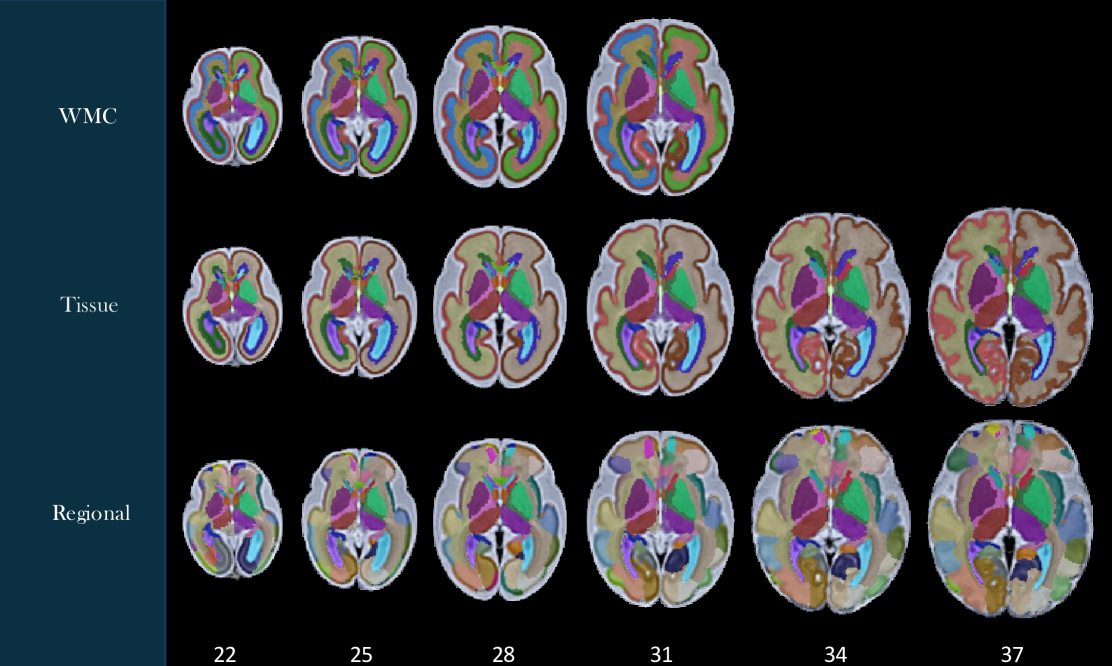

Labels were generated on the spatiotemporal fetal brain MRI atlases following the procedure described in the Methods section. As illustrated in Figure 4, these labels include 1) the transient compartments of the developing white matter (WMC) for all atlases less than 32 weeks, 2) tissue types, and 3) regions. For details of these labels, we refer to the text files in the data repository. Figure 5 shows the fetal DTI atlas [24] (color anisotropy in the first row) along with its tissue segmentations (second row) and regional parcellations (third row) that are released in this edition with the CRL-2025 atlas. All of the segmentations and labels on the T2w atlas were carefully checked, manually refined, and validated in multiple rounds by four experts under the supervision of a neurologist and a neuroanatomist each with more than a decade of experience in assessing fetal neuroanatomy on MRI. All the segmentations on the DTI atlas were carefully checked, manually corrected, and validated by two experts with several years of experience in fetal neuroanatomy on MRI and dMRI. To further assess and validate the use of the atlases and their labels, we used the atlases for multi-atlas segmentation of individual subject fetal brain MRIs, and used multi-atlas generated, manually-corrected labels on individual subject images [22] to train and test deep learning based segmentation models (as discussed in the Methods section) and presented in the next section.

Refer to caption

Figure 4: Tissue and regional segmentations and structural labels overlaid on axial views of the CRL-2025 spatiotemporal fetal brain MRI atlas at six representative gestational age (GA) weeks. All label schemes have subcortical structures including lentiform and caudate nuclei, internal capsules, thalami, and hippocampi separately on each hemisphere. Tissue segmentation labels (middle row) delineate the cortical plate-white matter boundary, CSF, and subcortical structures. In the top row, the white matter of the tissue segmentation is divided into white matter compartments (WMC) including the ventricular and intermediate zones and the subplate. These transient WMCs gradually disappear and were not clearly observable on the atlases beyond 31 weeks. The bottom row displays regional segmentations which are useful for regional and connectivity analyses.